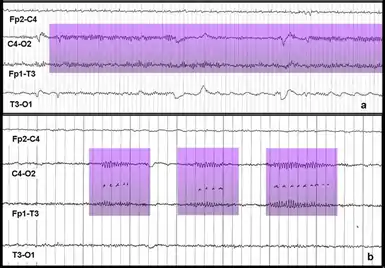

Интерфейсы мозг-компьютер (ИМК) — активно развивающаяся технология, которая, как полагают, однажды сможет дать бо́льшую независимость людям с инвалидностями. Предполагается, что эти технологии смогут помогать людям почти полностью или даже полностью парализованным, например с такими заболеваниями как тетраплегия (квадриплегия) или боковым амиотрофическим склерозом. ИМК могут помочь таким больным в общении или даже позволят контролировать движение инвалидных кресел и нейропротезов[7][17]. Одним из типов МКИ является интерфейс, использующий событийно-связанную десинхронизацию мю-ритма для управления компьютером[7]. Этот метод мониторинга активности мозга основан на том факте, что когда группа нейронов находится в состоянии покоя они, как правило, возбуждаются синхронно. Если оператор МКИ мысленно представит движение («событие»), произойдёт десинхронизация (связанная с «событием»). Нейроны, которые до этого возбуждались синхронно, приобретут свои индивидуальные, не похожие друг на друга паттерны возбуждения. Это приведёт к уменьшению амплитуды регистрируемого сигнала, которое может быть зафиксировано и проанализировано при помощи компьютера. Операторы подобных МКИ тренируются визуализировать движения ногами, руками и/или языком. Эти части тела имеют удалённые друг от друга проекционные зоны коры головного мозга и поэтому их легче всего отличить друг от друга на основе записей электроэнцефалограммы (ЭЭГ) или электрокортикограммы (ЭКоГ) с электродов размещённых над моторной корой[7][18]. Событийно-связанная десинхронизация может быть использована вместе с другими методами мониторинга электрической активности мозга, позволяя создавать гибридные ИМК, которые часто оказываются более эффективными, чем ИМК использующие только один метод мониторинга[7][18].